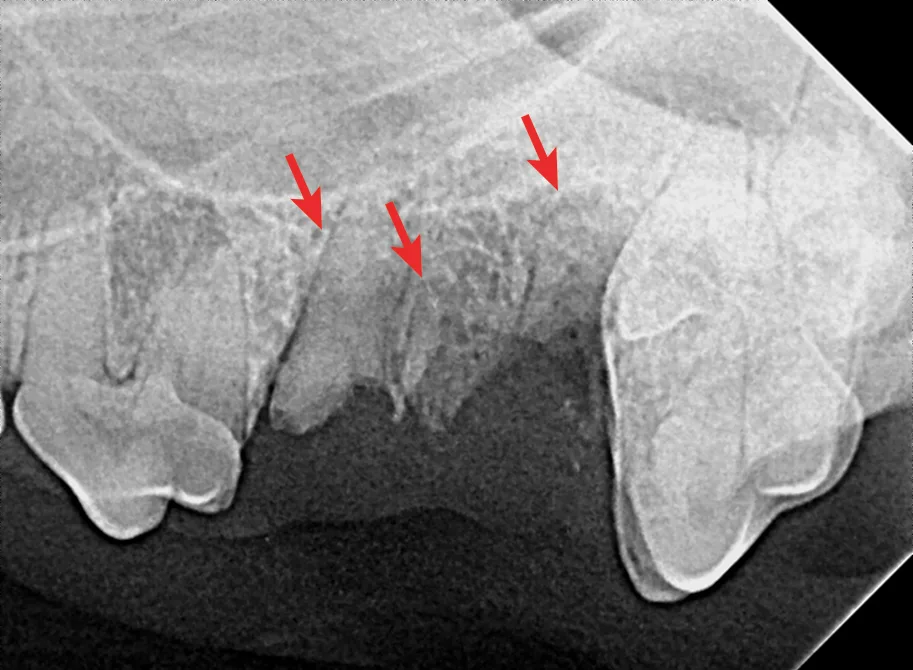

Dental X-ray with arrows pointing to root fractures of the 4th maxillary premolar in a dog.

FIGURE 1

Fracture of the mesiobuccal and distal roots (arrows) during extraction of the left maxillary 4th premolar tooth in a dog